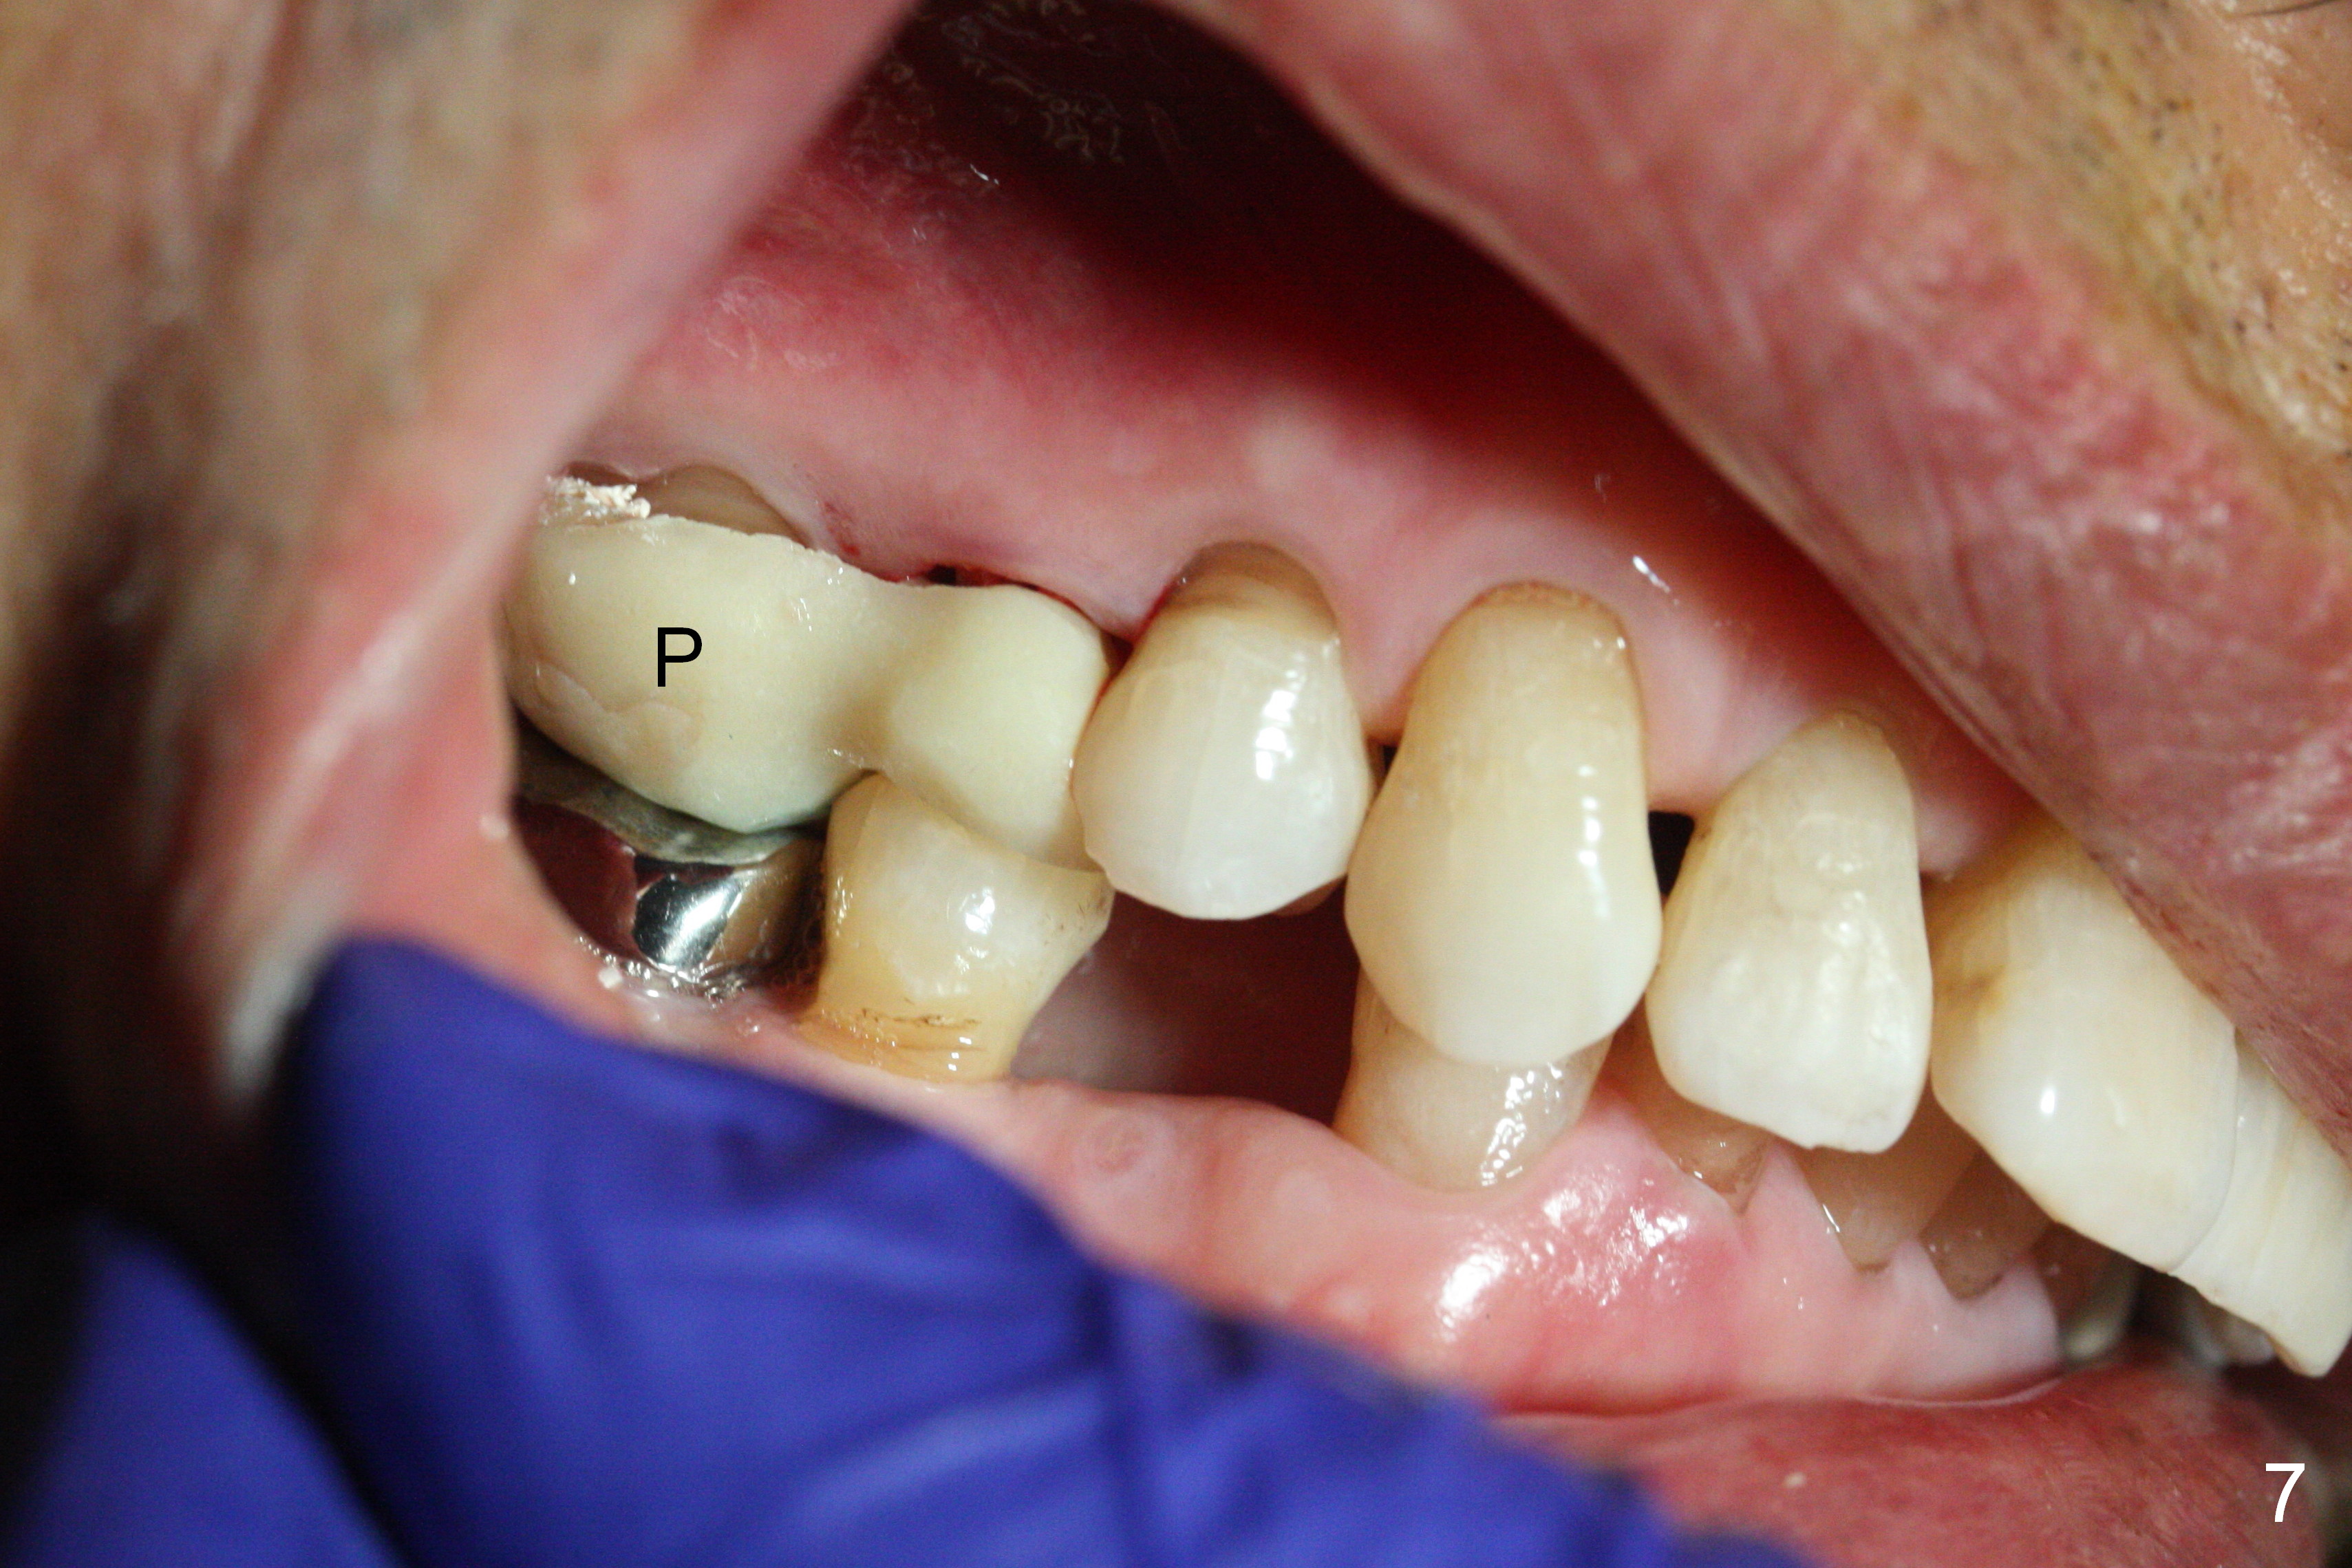

Preop exam shows posterior occlusal collapse (Fig.1) with #3 lost crown and #4 residual root. There is no ridge atrophy at #2 buccopalatally (Fig.2). The root stump of the tooth #4 is oblong, apparently consisting of 2 roots (Fig.3). There is a pointed septum at #4 socket (Fig.4, severe palatal wear of the anterior teeth (^)). After the septum is flattened with surgical handpiece and #8 round bur, 1.6 mm drill is used to start osteotomy in the septum, followed by Magic Drills (MD) and Magic Expanders (ME) alternatively. Osteotomy at #2 is initiated with Magic split, followed by MD and ME in the same manner. Dummy implants are tried in (Fig.5). Because of limited vertical height, Magicore (5.5x9(1) mm) is placed at #2, while a 4x13 mm FC implant 1-2 mm deeper than usual at #4 (Fig.6, ~ 55 Ncm). When a 5x4(2) mm pair abutment is placed at #4, there is no clearance between the Magicore at #2 and the abutment and the opposing dentition. A splinted provisional is fabricated at #3 and 4 to increase the posterior vertical height (Fig.7 P,8). In fact the occlusal contact is confined to the portion of the provisional at #3. The provisional has to extend to #4 to keep bone graft (Fig.6 *) and collagen plug in place. Liquid food is recommended at least 2-3 weeks, since there is no functional occlusal contact on the left. When the wound heals at #4 approximately 2-3 weeks, the splinted provisional can be sectioned with removal the portion at #4 to reduce micro-movement. By the evening the patient is doing well without nasal hemorrhage (sinus lift at #2 (Fig.6 *) or TMJ disturbance (due to increased vertical height).